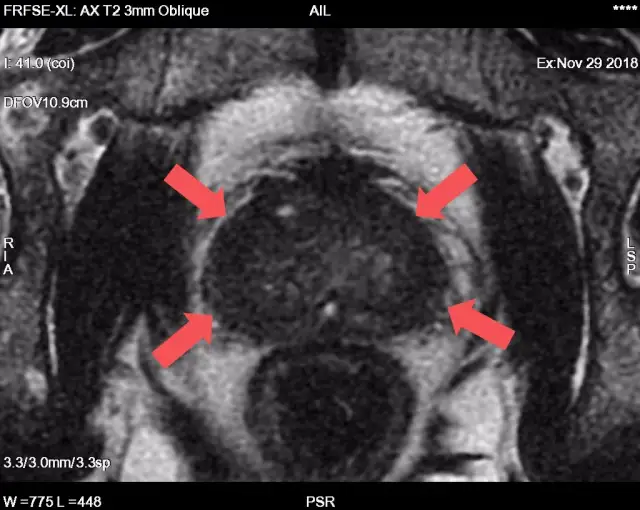

BadaniaJak przygotować się do badania prostaty? Poradnik krok po krokuAngelika Pawłowska-23 września 2025

BadaniaBadanie prostaty: Kompleksowy przewodnik - kiedy, jak i dlaczego?Ewa Chmielewska-22 września 2025

BadaniaBiopsja prostaty: Co musisz wiedzieć? Przebieg, przygotowanie, wynikiAngelika Pawłowska-21 września 2025